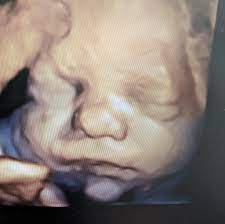

Sweet baby face louisville ky. March 1 2020. Sweet Baby Face is a 3D 4D Ultrasound and Baby Boutique in Louisville Elizabethtown KY. See your child in more depth and detail.

Pregnancy and Childbirth Service Near Sweet Baby Face. They give you a much clearer view of your child than the traditional 2D ultrasound you may even see if your baby has you or your partners features. Company Profile Contact information Current and former Employee directory Corporate history statetax IDs.

We do 2D 3D 4D HD5D elective ultrasound images in Louisville Elizabethtown. Millions of Products Top Brands. Combining cutting-edge technology with a spa theater environment we bring unbelievable images of your unborn baby to life.